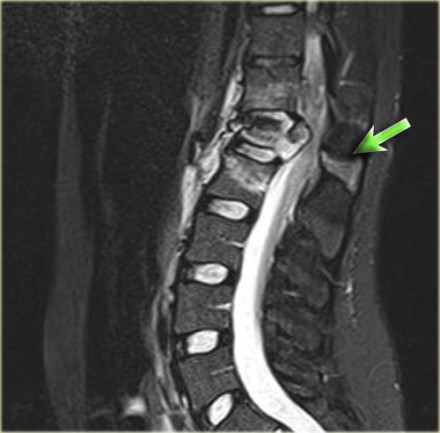

Look at the images.

What are the findings?

The findings are:

- Vertebral bodies show marrow edema as a result of a fracture.

- Torn flaval ligament (yellow arrow).

- Fractures through the posterior elements (red arrows).

The TLICS-score is high, because there is distraction and injury to the PLC.